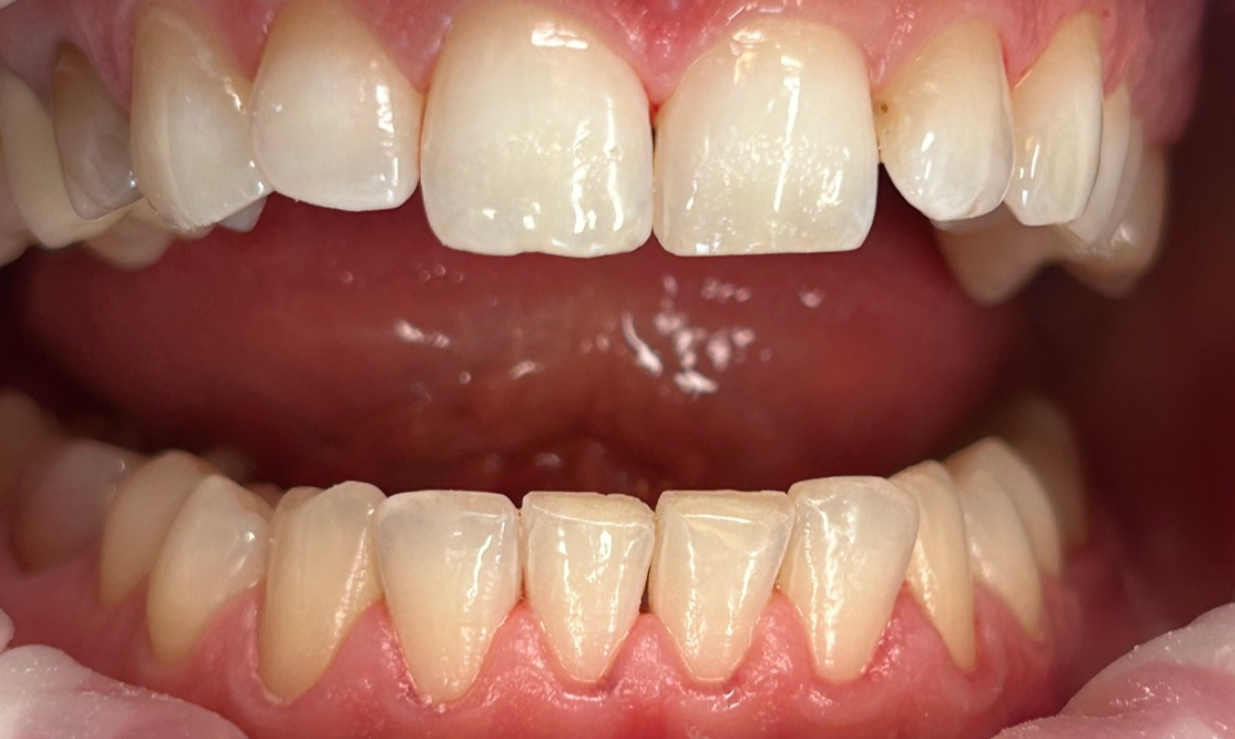

Zaprezentujemy serię poruszających historii pacjentów, którzy zdecydowali się na kompleksowe leczenie dentystyczne. Od przypadków zaawansowanej próchnicy, przez wypadki, które wymagały rekonstrukcji zębów, po pacjentów marzących o hollywoodzkim uśmiechu dzięki zastosowaniu licówek – każda historia jest dowodem na to, jak nowoczesna stomatologia może odmienić życie.

Skupimy się na innowacyjnych technologiach i metodach leczenia stosowanych w naszej klinice, które sprawiają, że te metamorfozy są możliwe. Od cyfrowego projektowania uśmiechu (DSD), przez ortodoncję i implanty, po zaawansowaną chirurgię szczękowo-twarzową. Omówimy, jak te techniki pracują razem, aby osiągnąć najlepsze wyniki.